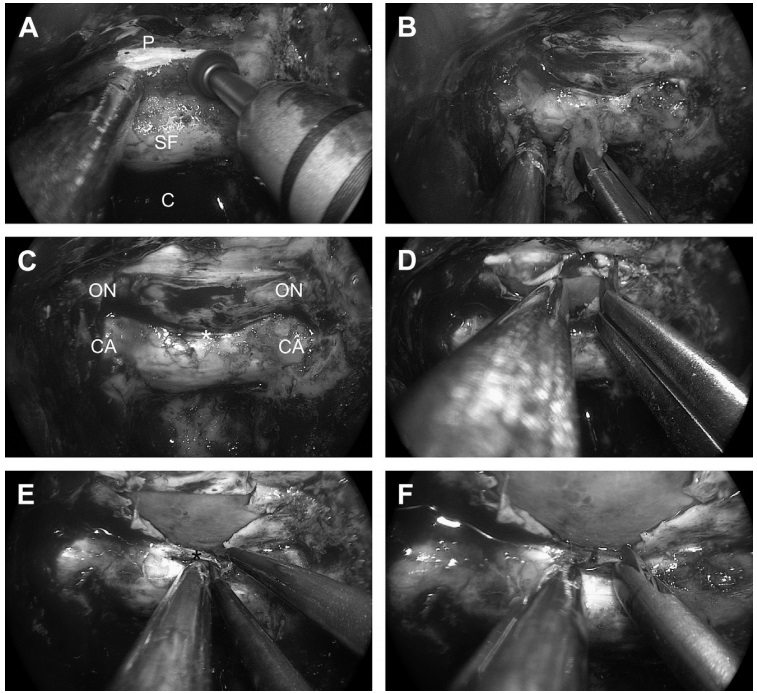

![图15为打开蝶骨的阶段。(A)蝶鞍底(SF)和蝶面(P)在蝶腔内的蛋壳样钻孔。(B)去除薄骨层。(C)全骨切除后显露硬脑膜的全景图,并标记视神经(ON)、颈动脉(CA)和海绵窦内上方(SIS[星号])的位置。(D)鞍上间隙硬脑膜开口。(E)海绵窦内上方凝固。(F)海绵窦内上方截面。](https://www.incsg.cn/uploads/allimg/240130/1-240130101404954.jpg)

图15为打开蝶骨的阶段。(A)蝶鞍底(SF)和蝶面(P)在蝶腔内的蛋壳样钻孔。(B)去除薄骨层。(C)全骨切除后显露硬脑膜的全景图,并标记视神经(ON)、颈动脉(CA)和海绵窦内上方(SIS[星号])的位置。(D)鞍上间隙硬脑膜开口。(E)海绵窦内上方凝固。(F)海绵窦内上方截面。